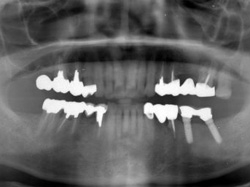

両側5歯症例

両側5歯症例両側5歯症例両側5歯症例 主訴-義歯のバネが壊れて手前の歯が痛んできた。 術前(旧義歯装着、鏡像) 術前(下顎粘膜面、鏡像)術前(下顎粘膜面、鏡像)術前(下顎粘膜面、鏡像) 術前レントゲン術前レントゲン術前レントゲン 術前口腔内(正面観)術前口腔内(正面観)術前口腔内(正面観)

術後(鏡像)術後(鏡像)術後(鏡像) 術後口腔内(正面観)術後口腔内(正面観)術後口腔内(正面観)もう入れ歯は要らなくなりました。 術後レントゲン術後レントゲン術後レントゲン